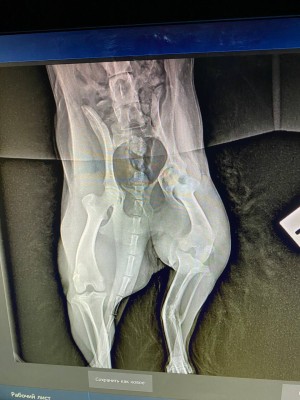

Сходили к ортопеду, у Люси перелом лапы в трех местах, уже сросшийся. Предлагают операцию в 2 этапа.

вот это перелом...она не под машину или какой транспорт попала, интересно. У нее получается в нижнем переломе верхняя часть кости срочлась с серединой нижнего обломка?

Похоже, что под машину. Когда ее нашли, видимо, свежий был перелом. Но пока волонтеры там мумили, хотя мы сразу согласились забрать, срослось все наперекосяк(Анастасия Нибелунг писал(а): ↑10 апр 2026, 20:33 вот это перелом...она не под машину или какой транспорт попала, интересно. У нее получается в нижнем переломе верхняя часть кости срочлась с серединой нижнего обломка?

Оксана ездила с Люсей ещё раз в Колпино на консультацию:

Возможно будет 3 этапа операций, поскольку у Люсьенки по КТ стало понятно , что еще повреждена голень, вывернута неестественно вправо.

Первый этап не меняется. Начинаем с таза, делают резекцию, если правильно запомнила. Реабилитация 2-4 месяца. Смотрим по итогу как встанет лапа, возможно, нам повезет и больше операций не потребуется. Стоимость первого этапа 30 тыс.

Если после первой операции и реабилитации понимаем, что лапа не встала до конца в естественное положение, следующий этап колено. Опять реабилитация, смотрим итог. И если снова лапа не выравнивается, дальше чиним голень. Но мы держим кулачки и надеемся, что обойдемся одной операцией, максимум двумя